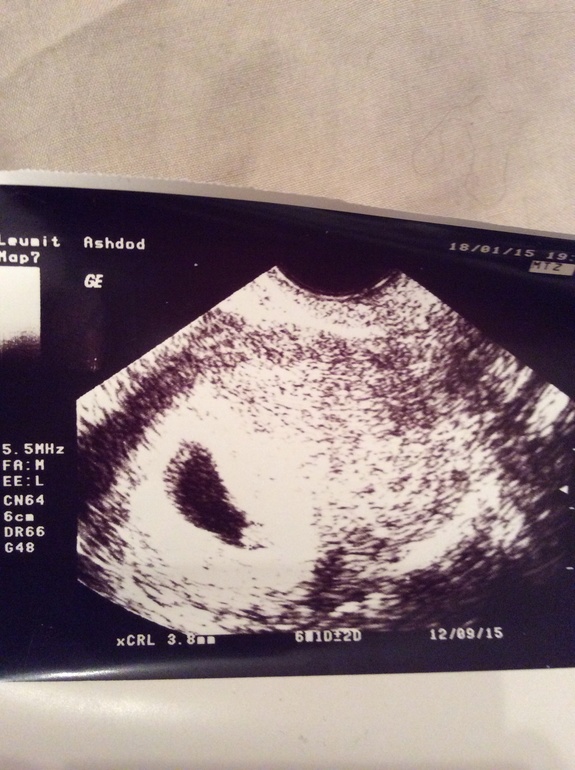

Узи и наконец поставили точный срок

Вначале врач сказал один срок беременности теперь на неделю меньше. Итого 6 недель и 2 дня. Есть сердцебиение

В прошлый раз не было.. Хотелось бы расшифровать что означают данные на узи. Единственное я поняла что бусинка 3.8 мм